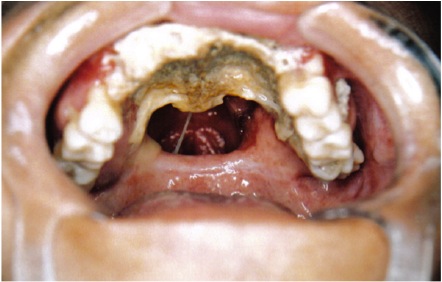

结外鼻型NK/T细胞淋巴瘤在形态学上多种多样,特征是血管中心性浸润,常伴有血管破坏和组织坏死,主要表现就是面部中线结构的毁损性破坏,所谓面部中线结构,就是在面部中间的那些结构,比如鼻腔、硬腭、口咽等。以前由于对这种病缺乏认识,而病理诊断也困难,于是将所有这类发生在面部中线结构并以坏死性病变为主的疾病诊断恶性中线网状细胞增生症,也被称为致死性中线肉芽肿,血管中心性免疫增殖性病变。后来才搞清楚,它其实是一种NK/T细胞来源的恶性淋巴瘤。

图片来源网络,仅供参考

3、局部典型表现:原发于鼻腔的NK/T细胞淋巴瘤局部主要的表现就是持续性进行性加重的鼻塞、鼻出血,伴有异味的分泌物增多。由于鼻部的组织广泛坏死,脱落,溃疡形成,鼻部和口腔的分泌物出现恶臭,像这例咨询中提到的就是鼻子和嘴之间腐烂了。后续还可能鼻中隔和硬腭部位的坏死穿孔,出现眼球突出,面部肿胀,声嘶,耳鸣,听力下降等。